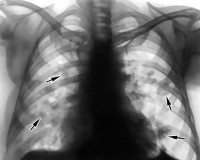

• Рентгенологические исследования. На рентгенографии органов грудной клетки можно выявить признаки уплотнения легочной ткани в виде сетчато-узелкового или сетчатого поражения. Там же обнаруживаются признаки плеврита и изменения контуров сердца при гидроперикарде. Рентгенография не является основным методом диагностики, поскольку патологические изменения выявляются лишь в 20% случаев синдрома.